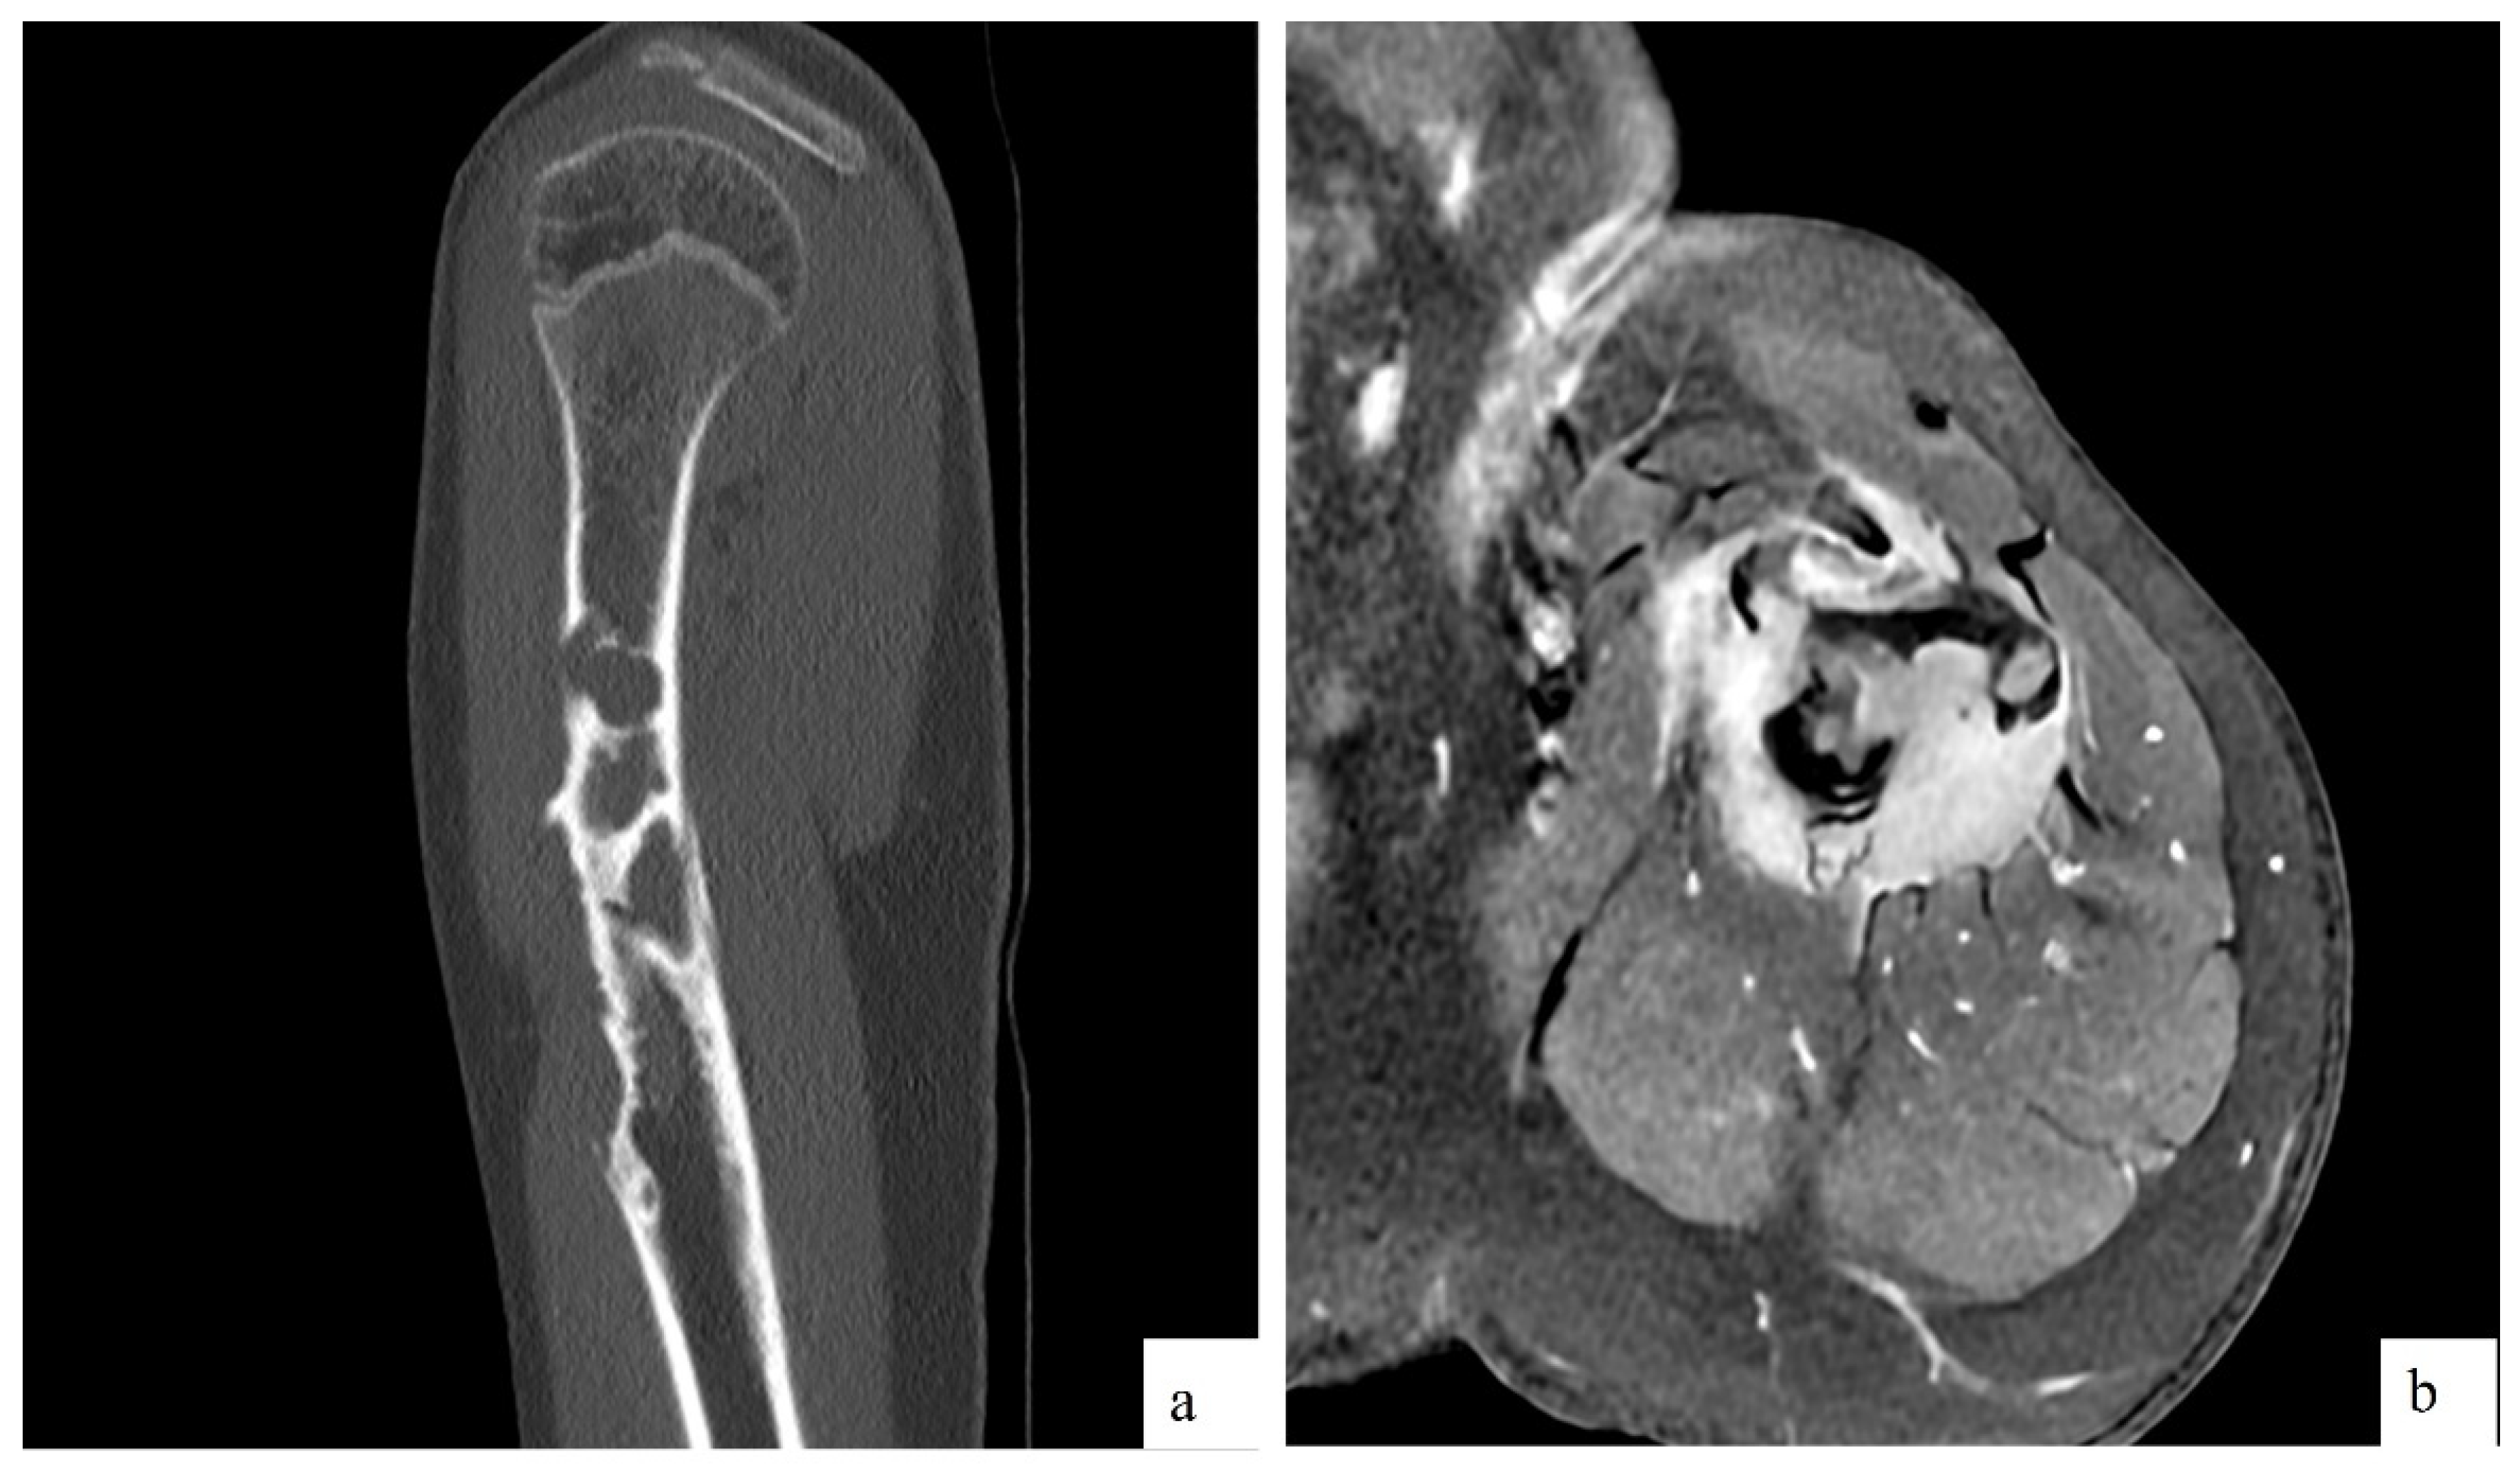

The MRI revealed a pathological fracture of the proximal humerus with angulation, located over a poorly defined lytic lesion in the proximal diaphysis, measuring approximately 17x72 mm. There was a cystic area of 13 mm in its proximal portion, cortical erosion, and intense contrast uptake. The findings suggested a differential diagnosis of fibrous dysplasia (FD), aneurysmal bone cyst (ABC), Ewing sarcoma (ES), and osteosarcoma (OS). Additionally, there was edema and contrast uptake in the adjacent musculature, which could be secondary to inflammatory changes due to the fracture, although infiltration could not be ruled out (Figure 1). Given these findings, the patient was referred to our center and was admitted for further evaluation.

Figure 1. a) CT findings: Sagital reconstruction showing diaphyseal lytic lesion with cortical erosion, causing bone remodelation. b) MRI findings: Post contrast transverse T1 sequence showing surrounding soft tissue mass with homogeneous and intense contrast uptake.